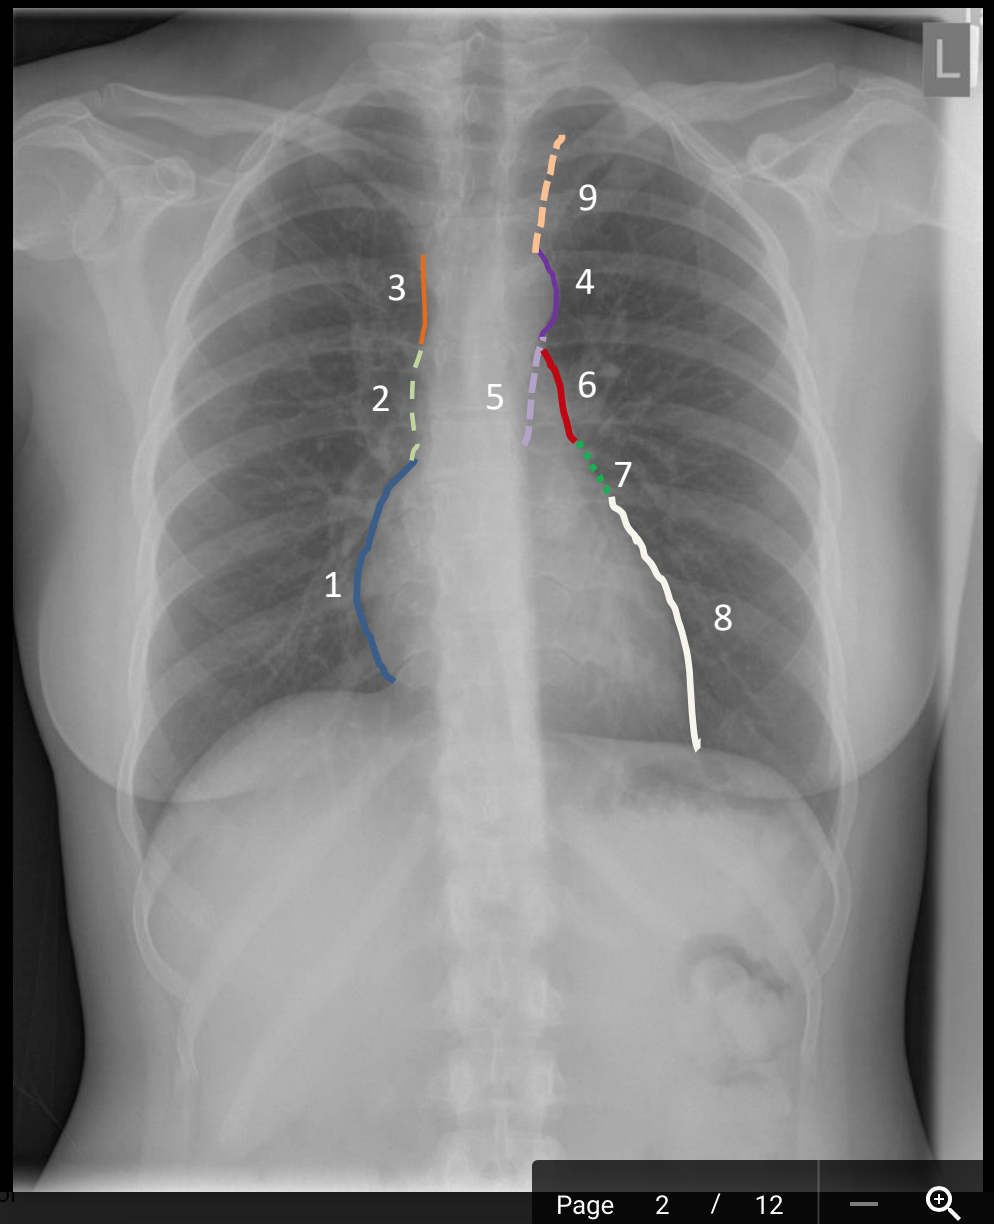

What is 9?

possibly common carotid a. or internal jugular v.

What is 8?

left ventricle

What is 7?

left atrial appendage (auricle)

What is 6?

pulmonary trunk

What is 5?

descending thoracic aorta

What is 4?

aortic knob/knucle (arch)

What is 3?

superior vena cava

What is 2?

ascending aorta/superior vena cava

What is 1?

right atrium